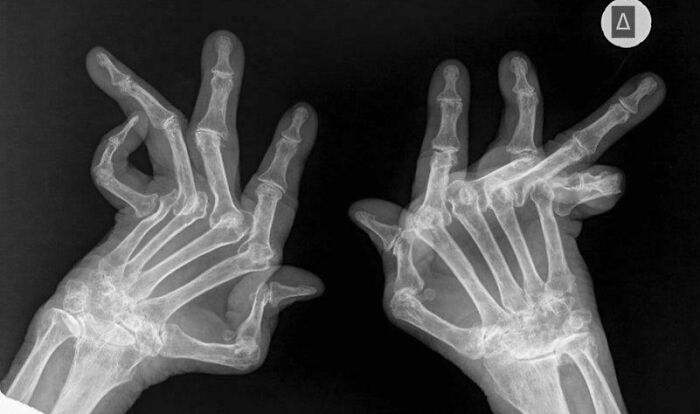

#9 What Severe Rheumatoid Arthritis Looks Like

Image credits: Educational-Eye9518